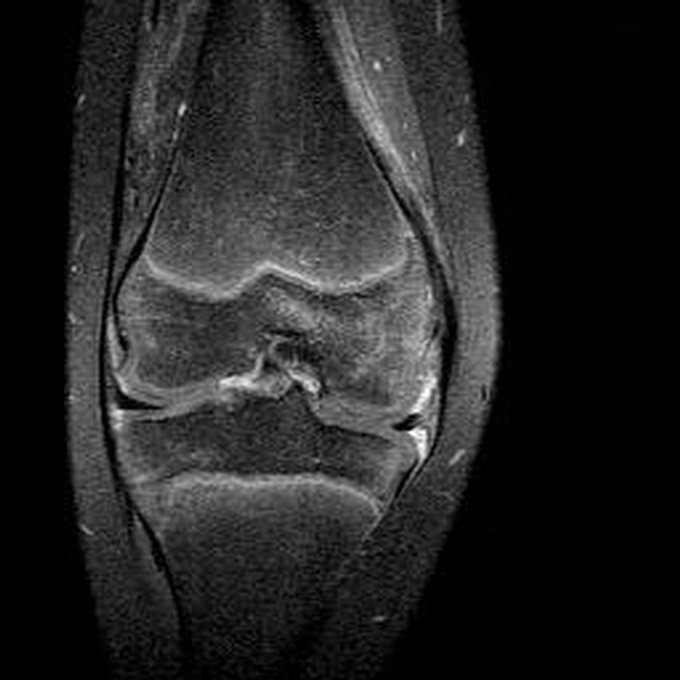

Haemophiliearthropathie bei Haemophilie A.

Arthropathia ARC123 Haemophiliearthropathie bei Haemophilie A.

MRT (high)